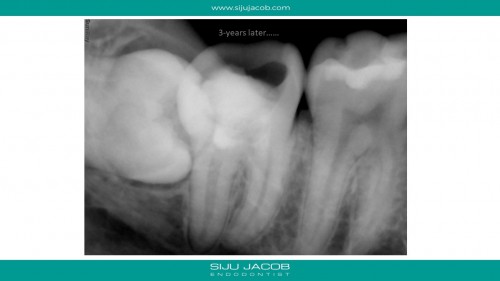

Apexogenesis + Selective Endo

By Siju Jacob / June 27, 2018

Patient was to be reviewed 2 weeks after initial treatment. Turned up after 3 years. […]